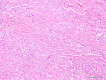

Eosinophilic angiocentric fibrosis (EAF) is an exceedingly rare and potentially disfiguring and obstructing benign lesion involving the upper airways. We report two cases of EAF originating from the nasal cavity in a 31-year-old female and a 58-year-old male exhibiting nasal obstructive symptoms, with imaging features and histopathology characteristic of EAF. Surgical excision was performed on one patient with a disfiguring nasal mass at a tertiary referral rhinology practice within a university centre. Summarized are the relevant clinical issues to increase awareness of this disease. The slow progression and rarity of the disease has previously resulted in diagnostic difficulty. We review the limited current literature surrounding the clinical features and treatment options for this progressive and potentially morbid condition. These cases reinforce that, while rare, inflammatory and fibrosing lesions in general should still be considered as part of the differential diagnosis in patients presenting with obstructive lesions in the sinonasal tract.